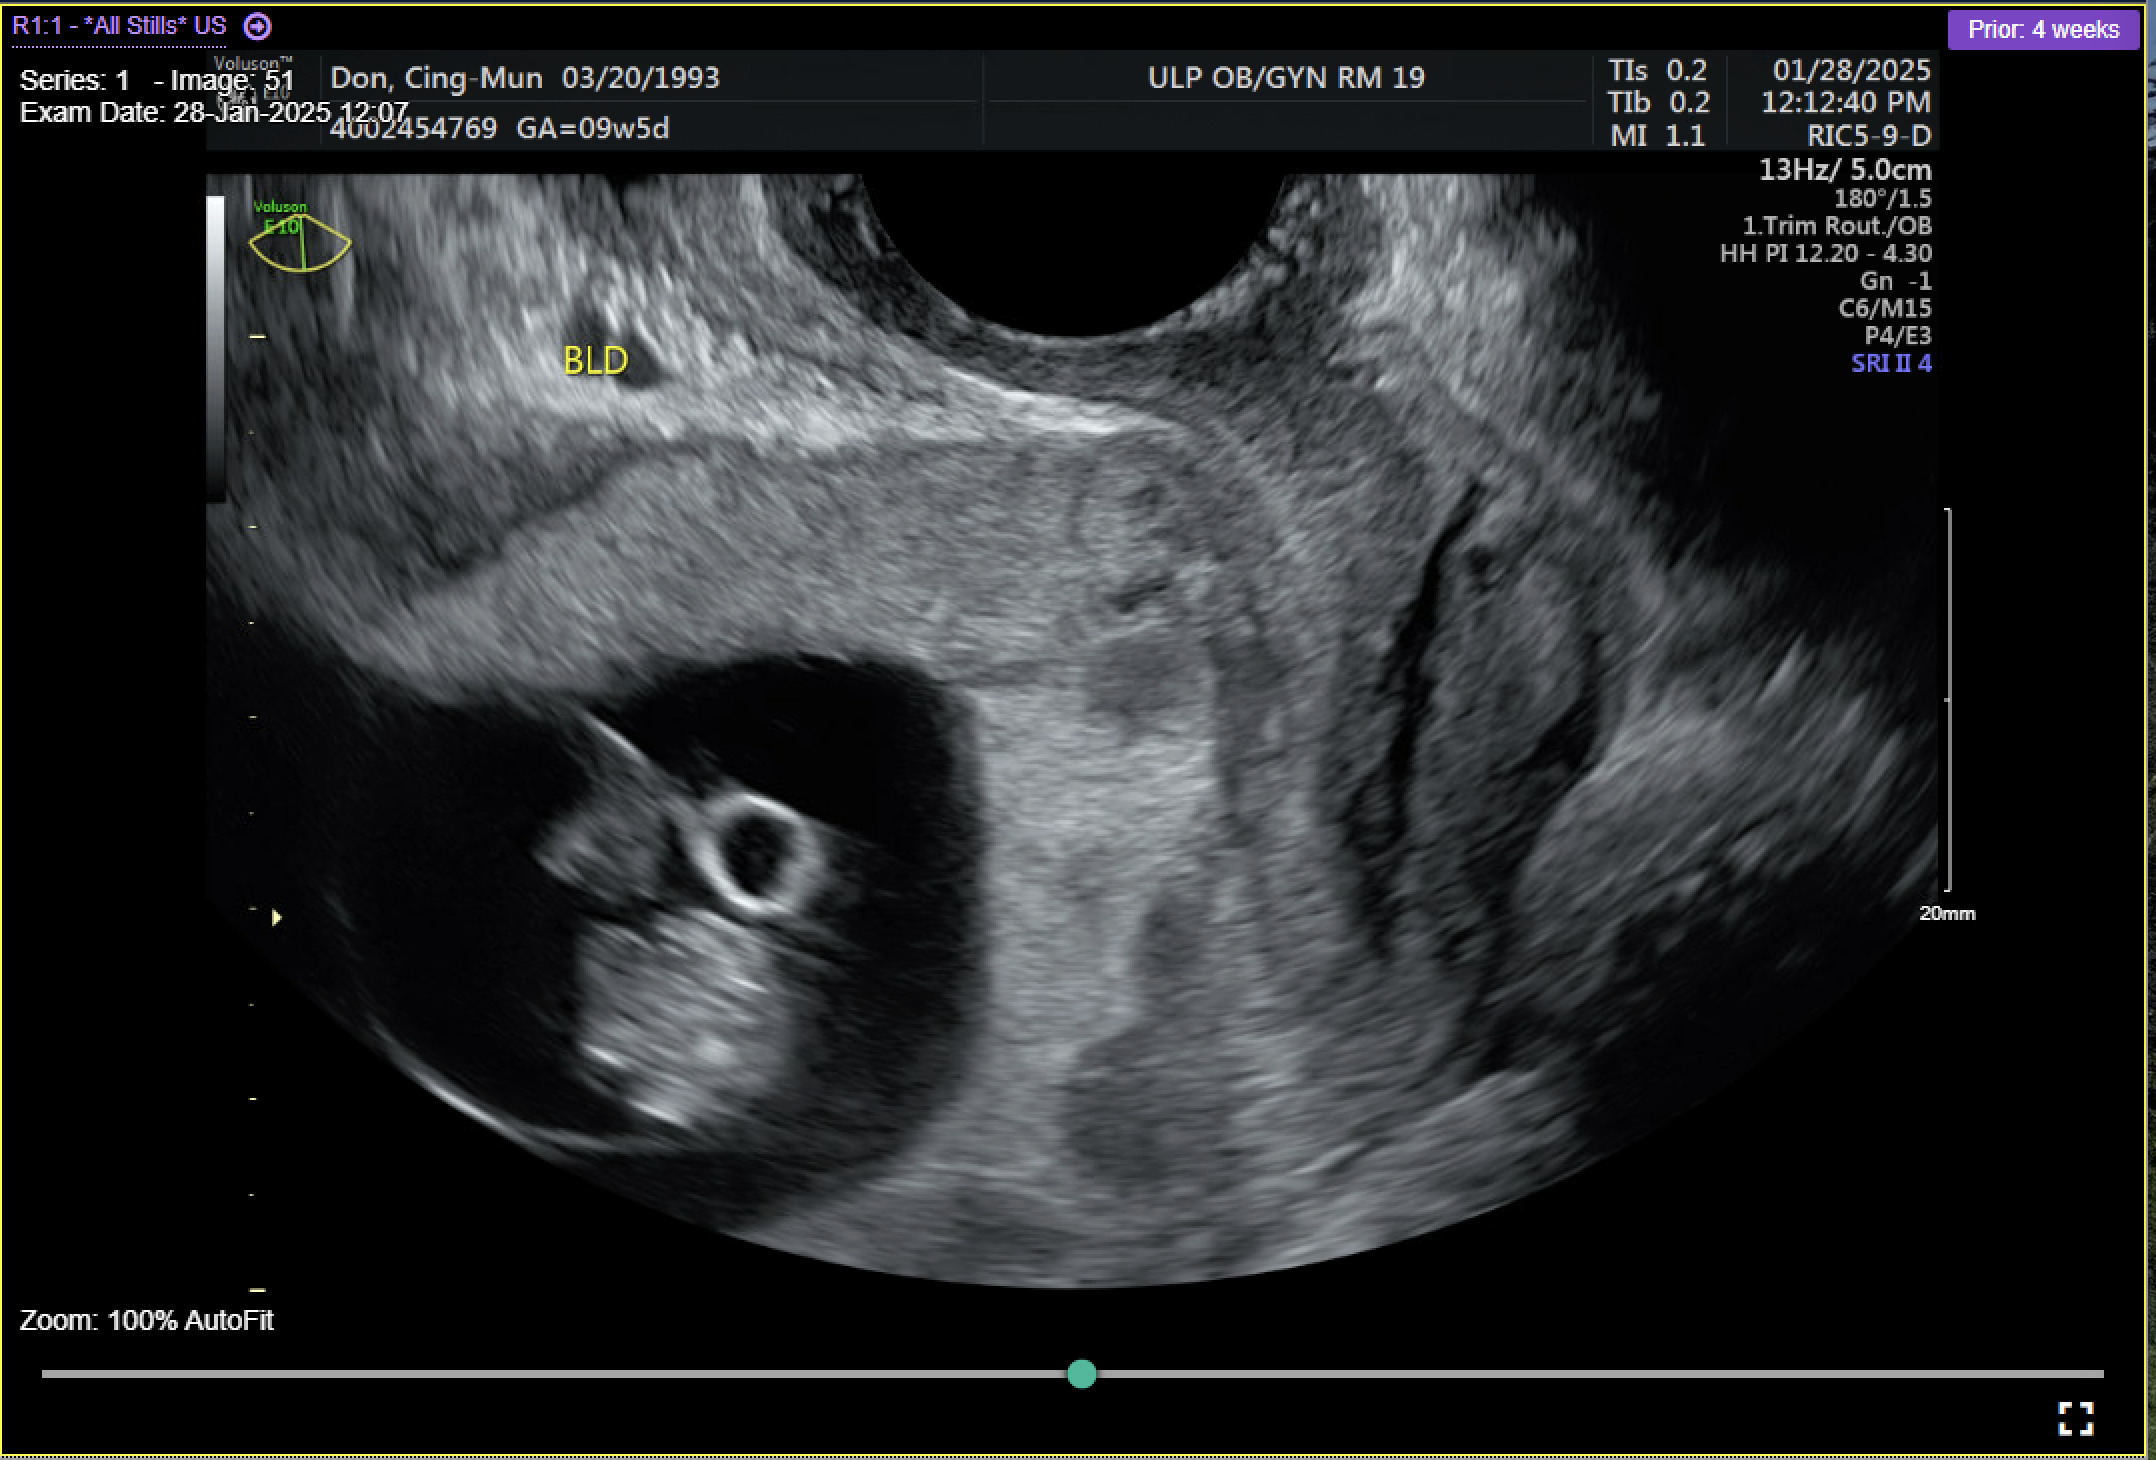

Results

A 31-year-old gravida 2 para 1001 at 13 weeks and 6 days gestation by a 7-week ultrasound presented to ULH for surgical management of a missed abortion in the setting of suspected CSP versus PAS. The patient had previously been seen at an outside hospital emergency room for concerns of bleeding and pelvic pain. Ultrasound workups for these concerns were significant for viable intrauterine pregnancy and moderate subchorionic hemorrhage superiorly, grossly measuring 5 cm at the largest dimension. Two weeks after her initial emergency department (ED) visit, the patient was seen in our practice’s general obstetric clinic. A first trimester ultrasound was performed at this time and again demonstrated a 5 cm subchorionic hemorrhage (Figure 1). At this time, concern for CSP versus PAS was also noted, and the patient was advised to return for a follow-up scan. When the patient returned for further evaluation of placental pathology, ultrasound revealed fetal demise with absent fetal cardiac activity (Figure 2). Following discussion with the maternal fetal medicine (MFM) provider, the patient ultimately elected for surgical evacuation of the products of conception to mitigate spontaneous bleeding risks in the setting of CSP versus PAS.